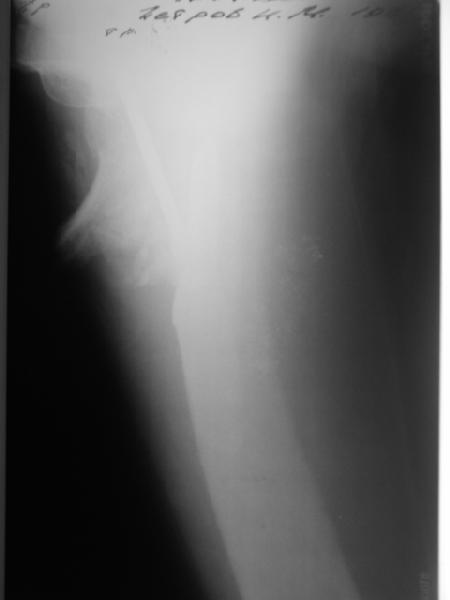

В приложении пример пациента, близкого по картине к тому, что представил Виктор (варус и смещение периферического отломка на поперечник кзади). Сделали как раз то, что Виктор исходно намеревался - аппаратная коррекция и затем гамма.